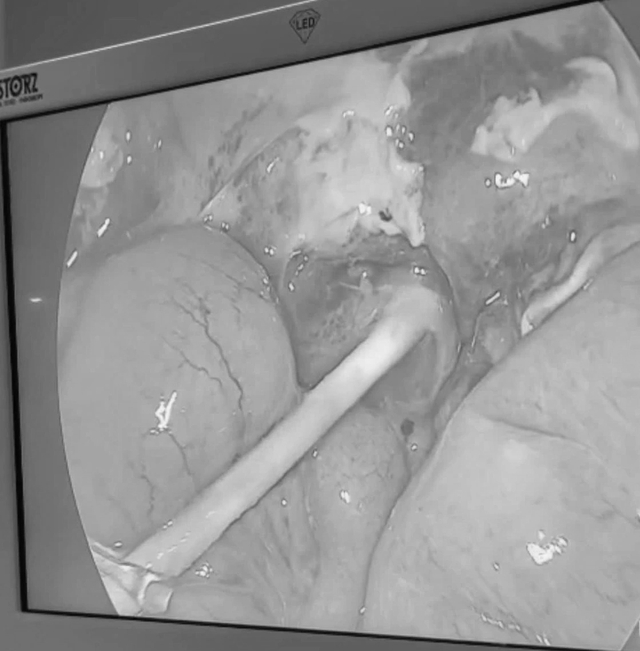

Dị vật dạng ống nhựa cứng, dài khoảng 6 cm, đã đâm xuyên mặt dưới tá tràng của bé H.T.N

ẢNH: BVCC

Qua thăm khám kết hợp các xét nghiệm cần thiết, bác sĩ chẩn đoán bé bị viêm phúc mạc nặng, chỉ định phẫu thuật khẩn cấp nhằm ngăn ngừa nguy cơ biến chứng nguy hiểm.

Trong quá trình phẫu thuật nội soi, ê kíp ghi nhận ổ bụng có nhiều dịch mủ đục lan tỏa. Nguyên nhân được xác định là một dị vật dạng ống nhựa cứng, màu trắng, dài khoảng 6 cm đâm xuyên mặt dưới tá tràng. Sau 15 ngày điều trị tích cực, tình trạng sức khỏe của bé ổn định, ăn uống bình thường, vết mổ khô và lành tốt.